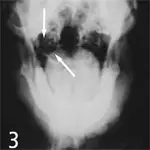

3. Magnified view of a normal feline tympanic bulla